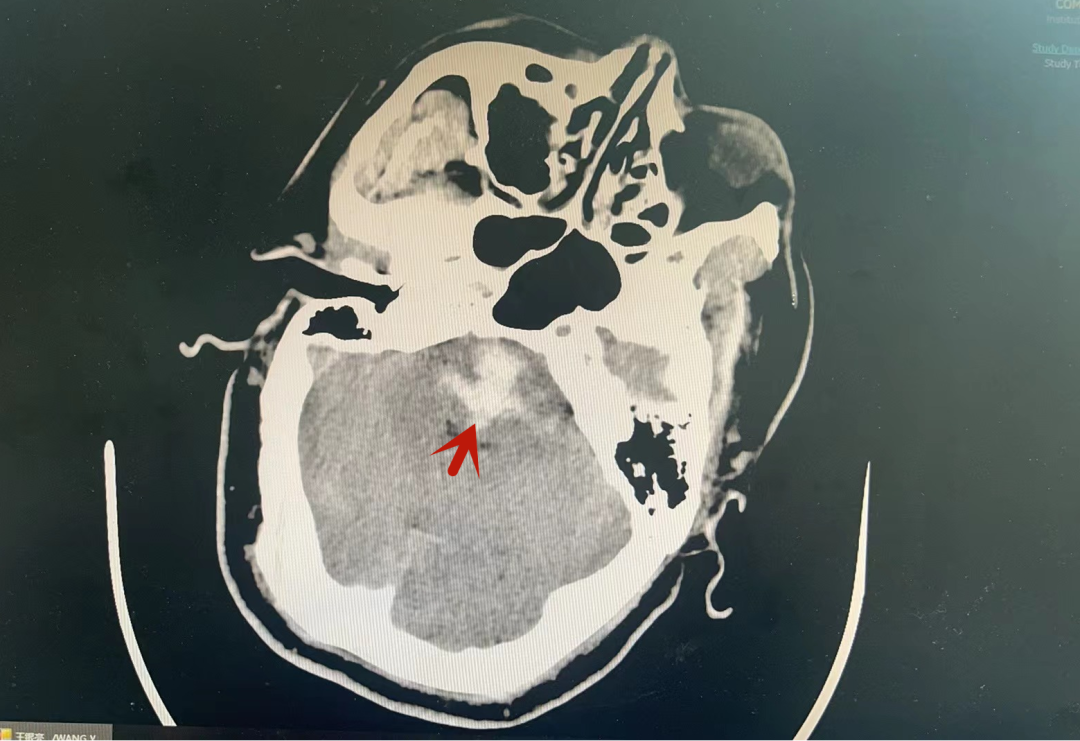

▲CT检查显示:脑干出血

神经内科二病区值班主治医生魏睿经过详细问诊及查体,发现杨先生有多年高血压病史,就诊时处于意识昏迷状态,肢体偏瘫,呼吸急促,指脉氧饱和度持续下降,心率增快。急诊头颅CT检查显示:脑干出血。医护人员立即给予控制血压、脱水降颅压等相关治疗后,将杨先生转入神经内科重症监护病房(NICU)接受进一步治疗。